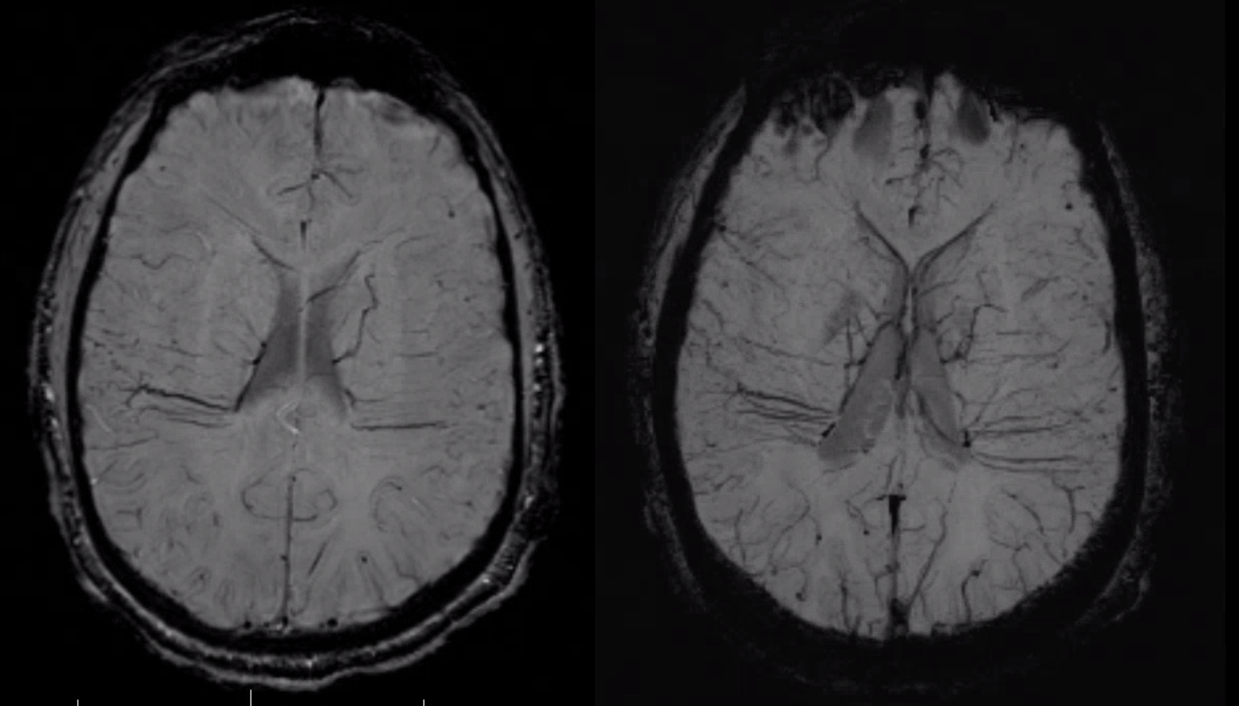

Another compensation for hypoplasia of the SSS is shift of superficial drainage into the deep venous system via the medullary veins draining into the internal cerebral veins. Courtesy Dr. Gopi Nayak. There is hypoplasia of the Superior Sagittal Sinus.

As one way of compensation for this superficial venous system deficiency, there is more venous drainage routed to the deep system. Amazing images of deep medullary/transverse venous prominence — completely nonpathologic, simply reflecting a shift of drainage equilibrium towards the deep venous system

Some arrows. Open white arrows — septal veins on the medial aspect of frontal horn. Thick white arrows — longitudinal caudate venous arcade. Black arrow — direct lateral vein, prominent because of hypoplasia of the posterior segment of the left longitudinal caudate vein. Thin white arrows are transverse/ medullary veins

Here is a diagrammatic way of showing the same thing